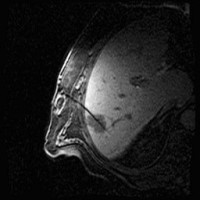

Under local anesthesia and administration of pain medication, the tumor is punctured under computer tomographic (CT), magnetic resonance imaging view with subsequent insertion of the catheters into the target volume.

Images: Brachytherapy for liver metastases: first MRI-guided placement of one catheter per tumor followed by irradiation through the catheters using Iridium 192 radiation source.